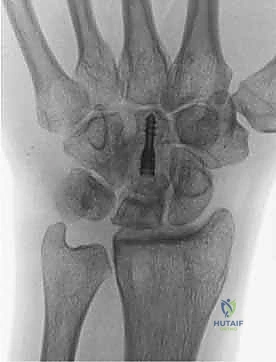

- الأشعة السينية (X-rays): هي الخطوة الأولى. في المراحل المبكرة جداً، قد تظهر الأشعة السينية طبيعية تماماً. في المراحل اللاحقة، يظهر العظم الهلالي بلون أبيض ناصع (متصلب)، ثم يبدأ في الظهور مفلطحاً أو متفتتاً.

- التصوير بالرنين المغناطيسي (MRI): هو المعيار الذهبي للتشخيص المبكر. يمكن للرنين المغناطيسي اكتشاف نقص التروية الدموية (وذمة العظم) قبل أشهر من ظهور أي تغيرات في الأشعة السينية. يعتمد الدكتور هطيف بشكل كبير على الرنين المغناطيسي لتحديد مرحلة المرض بدقة.

- التصوير المقطعي المحوسب (CT Scan): يُستخدم لتقييم مدى تفتت العظم الهلالي وبنيته ثلاثية الأبعاد، وهو أمر حاسم في التخطيط الجراحي.

الأستاذ الدكتور محمد هطيف، بفضل تدريبه المتقدم وخبرته الطويلة، يتبنى نهجاً جراحياً مركباً يُعد من أحدث ما توصل إليه الطب في هذا المجال، وهو الجمع بين إجراءين في عملية واحدة: تطويل العظم الوعائي (Vascularized Bone Graft) و تقصير العظم الكبير (Capitate Shortening Osteotomy).

3. يتم إعادة تثبيت العظم الكبير باستخدام مسامير دقيقة (Screws) أو دبابيس معدنية (K-wires).